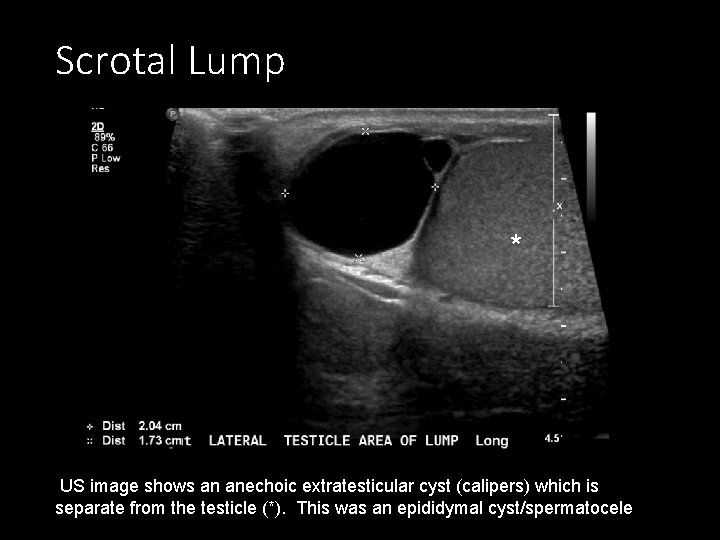

Ultrasound work up for a scrotal lump 1. Intratesticular or extra testicular? Extratesticular lesions are more commonly benign Intratesticular lesions are more commonly malignant 2. Solid or cystic (see “intro to rad path” module for review) Solid intratesticular lesions are worrisome 3. Single or multiple? If multiple, think mets/lymphoma (intro to rad path)

Scrotal Lump * US image shows an anechoic extratesticular cyst (calipers) which is separate from the testicle (*). This was an epididymal cyst/spermatocele